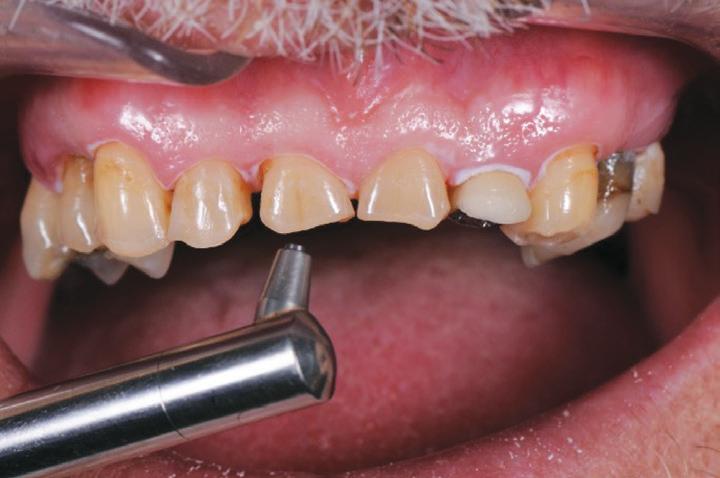

Restoring the Central Incisor (#11) first, enabled the Author to establish the midline position and correct length and form for the teeth. The remaining teeth were then built up one at a time, using the initial buildup of #11 as a guide (Figs. 14, 15).

Once the maxillary buildups were completed, the mandibular

teeth were then restored with the same tooth-by-tooth freehand approach, to establish the new vertical dimension and to allow the posterior teeth to be built into a stable occlusion (Figs. 16, 17).

Importantly, the stability of the occlusion was re-established with creation of occlusal contacts on each tooth, and the re-introduction of canine and incisal guidance, to control lateral and protrusive forces (Figs. 20, 21, 22, 23).